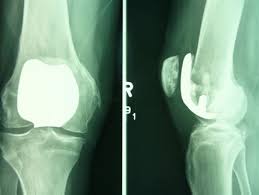

이 때에는 ‘인공관절 치환술’이 유일한 해결책으로 지목된다고 한다. 망가진 관절 대신, 그 자리에 새로운 관절을 이식하는 것이 바로 ‘인공관절 치환술’이라고 한다.

인공관절 수술은 원리에 따라 다양하게 나뉘며 닳아 없어진 무릎 연골 대신 인체에 해가 없는 코발트크롬, 티타늄합금 등의 금속이나 세라믹으로 만들어진 인공관절을 삽입하는 과정으로 진행된다고 한다. 다만 환자 입장에선 자신에게 적합한 수술법을 찾는 것이 더욱 중요해졌다고 한다.

완성된 출력물 즉, 관절 절삭 부위를 알려주는 ‘PSI(Patient Specific Instrument)’라는 절삭유도장치라고 한다. 수술 시 손상된 관절 부위에 PSI를 끼우고 망가진 관절을 잘라내면 인공관절이 정확한 자리에 이식된다고 한다.